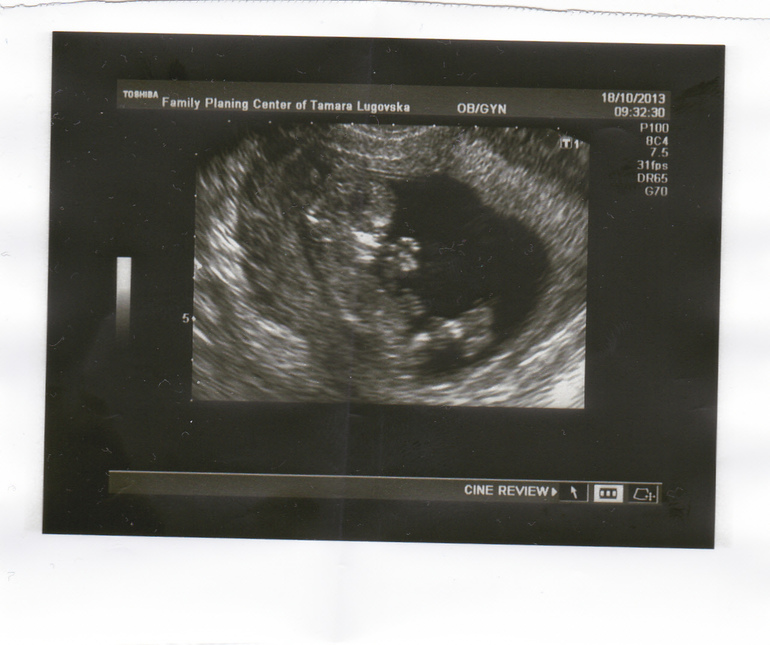

Первое УЗИ)))

Результаты: УЗИ, КТГ, доплера, скринингаПривет, роднулечки!))) Ну вот наконец-то вчера были на нашем первом УЗИ ( до этого не делала, тк. ничего не беспокоило) Несколько ночей мучалась бессонницей - все никак дожаться не могла заветного дня Х.

На стене висел большой экран, так что с мужем смогли вдоволь налюбоваться нашей кнопочкой! ТТТ все на хорошо, осталось только дождаться рез-тов крови.Малявочка так танцевал, ручонками махал, ножками дергал - я от умиления расплакалась. Наш папа был впечатлен, говорит невероятно... 65 мм.. а уже такой настоящий человечек.

Второй день хожу с идиотской улыбкой на лице, перед глазами ничего, кроме нашей крошечки)))